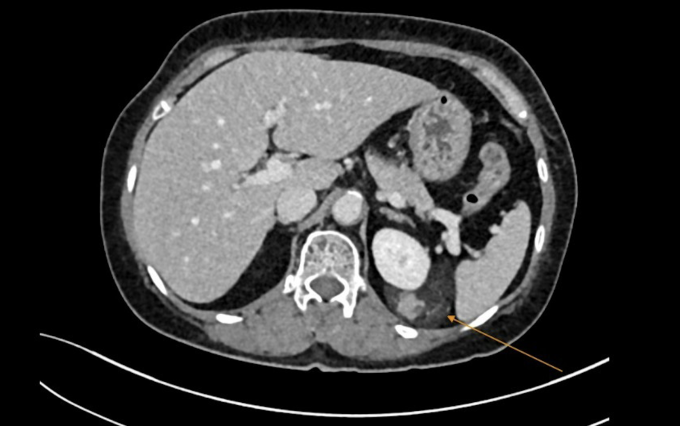

U kích thước khoảng 4×8 cm ở thận trái song bà Kim không đau, không sốt, không tiểu máu. Ảnh chụp cắt lớp vi tính (CT) cho thấy khối u xuất phát từ một phần nhu mô thận rồi lan rộng ra xung quanh, bao lấy thận, kèm theo nhiều mạch máu tăng sinh dị dạng.

Vị trí khối u cơ mỡ của bà Kim. Ảnh: Bệnh viện Đa khoa Tâm Anh